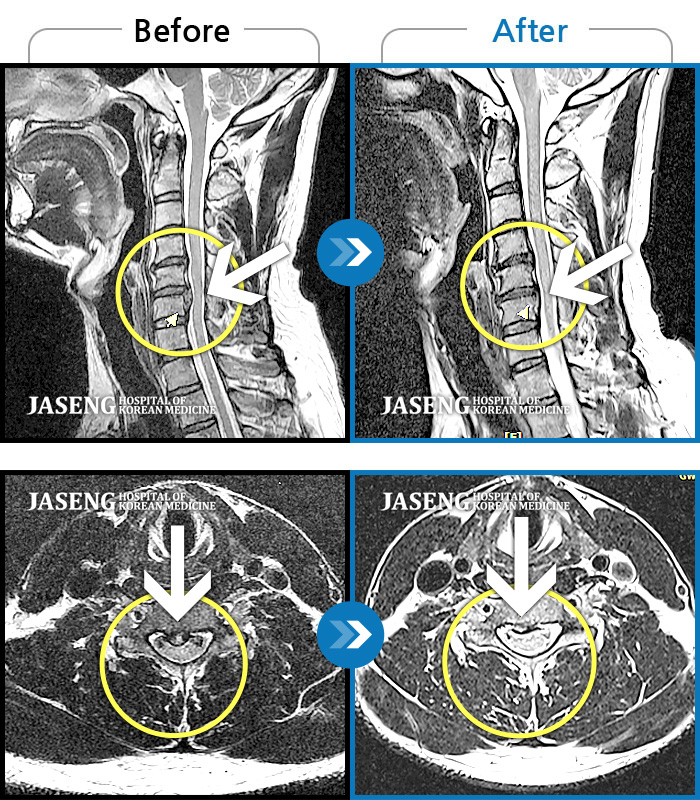

목디스크

광주 · 김동은 원장

후경부 통증 및 우상지 방사통

촬영시기

2019.12.05 ~ 2020.06.16

2020.06.19

조회수 575